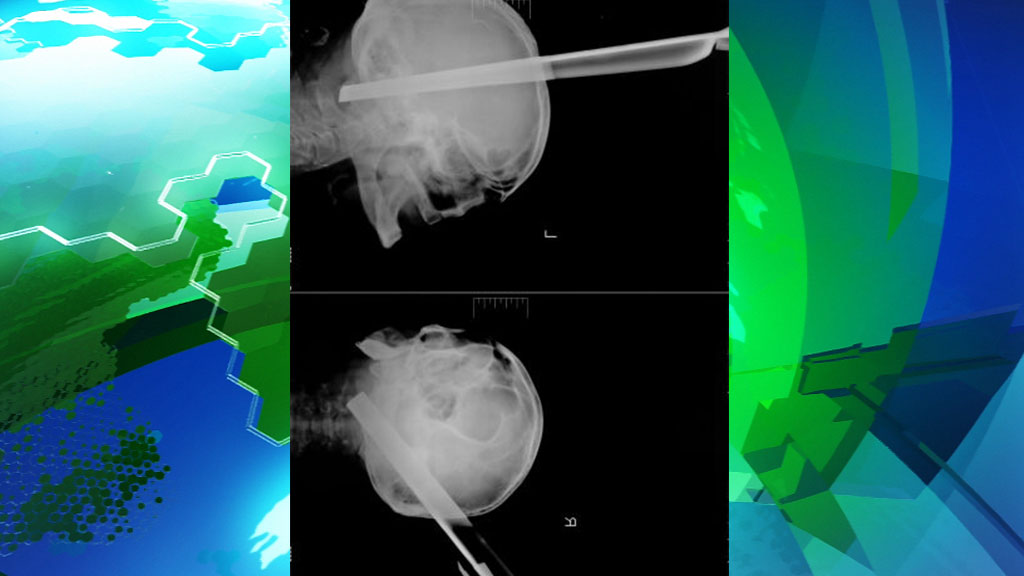

В Красноярске врачи спасли жизнь пациента, в голове которого по неизвестным причинам оказалась ножка металлического табурета.

Экстренная нейрохирургическая операция длилась около трех часов. По словам проводившего ее нейрохирурга Павла Руденко, пациент был прооперирован без осложнений, а после удаления столь массивного предмета у больного не возникло даже ожидаемого кровотечения.